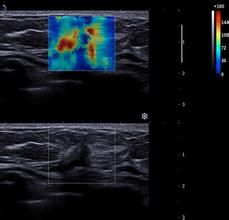

本病的早期發現、早期診斷,是提高療效的關鍵。應結合患者的臨床表現及病史、體格檢查、影像學檢查、組織病理學和細胞病理學檢查(在有條件的醫院),進行乳腺癌的診斷與鑑別診斷。

多數患者是自己無意中發現乳腺腫塊來醫院就診的,少數患者是通過定期體檢或篩查被發現乳腺腫物或可疑病變。觸及腫塊可採用針吸活檢或手術切除活檢明確診斷。若臨床摸不到腫塊是靠影像學檢查發現可疑病變,可藉助影像學檢查定位進行活檢,病理學檢查是乳腺癌診斷的金標準。